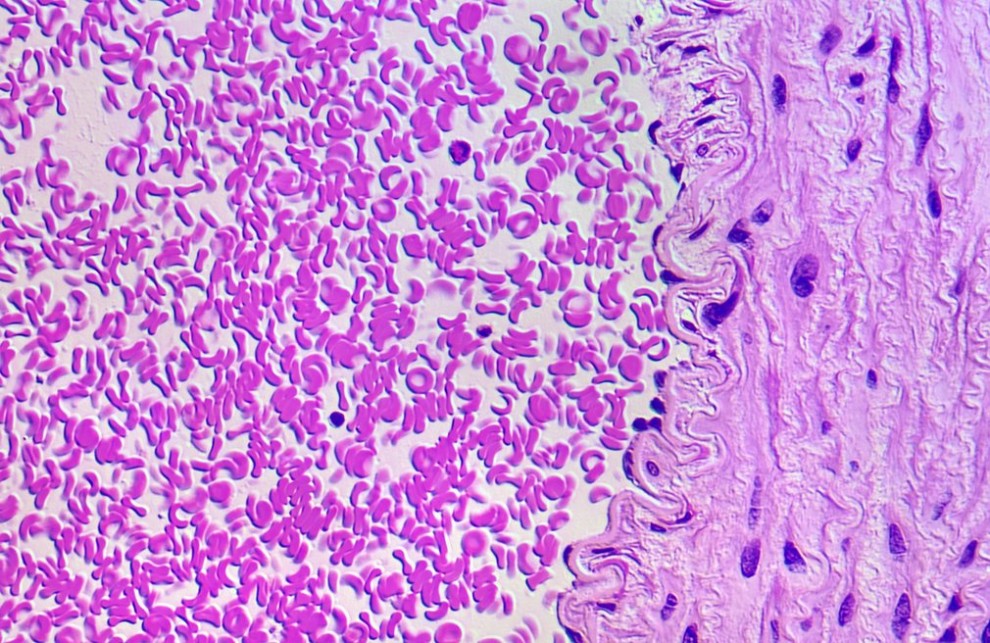

Участок стенки артерии примата толщиной 1,5 микрометра и кровь, окрашенная гематоксилином и эозином.